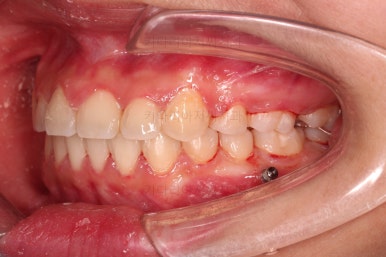

초진 시 입안의 모습을 보실게요.

결국은 앞니 사이에 틈이 생겼기 때문에 이같은 문제점을 인지하시고 내원하셨던거죠.

이번 환자분의 경우는 치아 결손 부위의 잇몸뼈도 양호했고 공간도 그리 크진 않았으며 윗니는 갯수가 1개 부족해도 교합을 맞추는데 문제가 거의 없기 때문에 시간이 좀 더 들더라도 임플란트 없이 앞니 사이 틈과 결손부위 틈새를 모아보기로 했어요.

부산치아교정 이번 치료의 핵심인데요.

결손 부위에 미니스크류를 이용해서 뒤쪽 어금니들을 결손 부위로 앞으로 앞으로 계속 당겨줍니다.